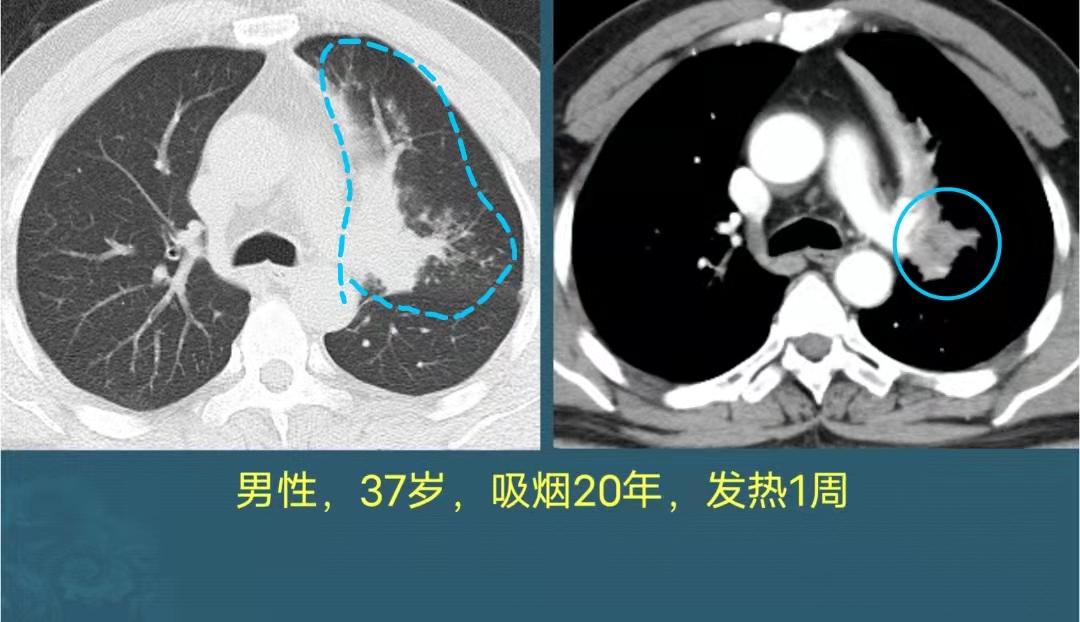

第一例,37岁男子,抽烟20年,咳嗽、发热1周,口服感冒药和“消炎药”无效,来医院做了胸部CT:

左肺上叶大片白色炎症,而且肺门区发现一个肿瘤(右图),把右肺上叶尖后段支气管堵塞了,这是中心型肺癌,并阻塞性肺炎。

万幸没有转移,及时做了左肺上叶切除+淋巴结清扫,病理是肺鳞癌(这种肺癌90%与吸烟有关)。

手术后6年复查,恢复很好:

人类一共有5叶肺,左边两叶右边3叶,他失去了左边一个肺叶,但成功推掉了地府归队通知,延长了几十年的地球寿命,很幸运!